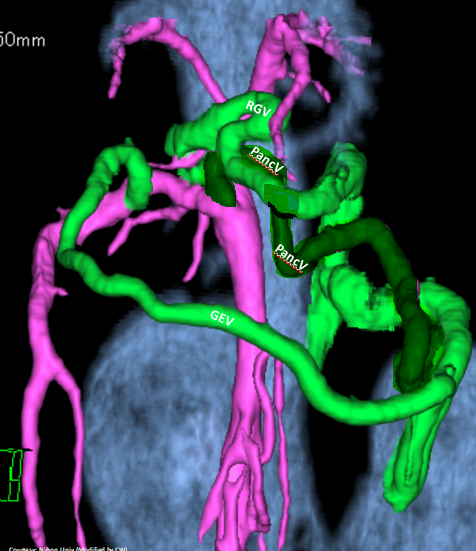

“LGA +RGV +GEV -GSV”

Left Gastric – Azygos Vein Shunt with Right Gastric Vein and (minor) Gastroepiploic Vein contributions with absent Gastrosplenic Vein (Does not enter PV)

WEISSE 2022